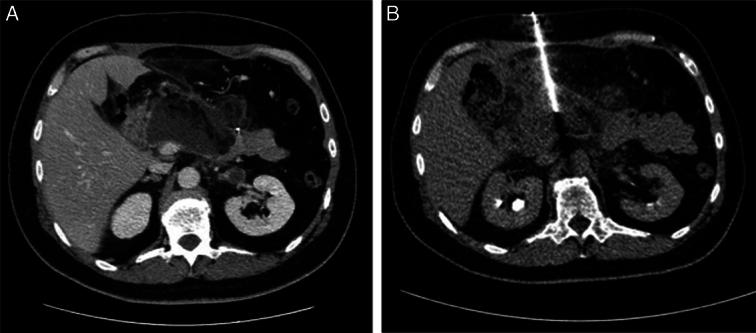

Postoperative pancreatic fistula (POPF) remains a common and dreaded complication after pancreatic resections and is associated with increased morbidity and mortality. Over the years, several different strategies have been investigated to prevent and mitigate POPF. However, when a POPF occurs, a consensus on the optimal management strategy of grade B and grade C POPF is still lacking, and the current management strategy is often based on local expertise and driven by patient's condition. Nevertheless, whereas the incidence of POPF after pancreatic surgery has remained stable, the overall mortality related to this complication has decreased over the years. This reflects an improvement in the management of this complication, which has become increasingly conservative. The aim of this review is to provide an updated evidence-based overview on the management strategies of POPF for surgeons and physicians in the clinical practice.

术后胰瘘(POPF)仍然是胰腺切除术后常见且可怕的并发症,与发病率和死亡率增加相关。多年来,人们研究了几种不同的策略来预防和减轻POPF。然而,当发生POPF时,对于B级和C级POPF的最佳管理策略仍缺乏共识,当前的管理策略通常基于当地的专业知识并由患者的病情驱动。尽管如此,虽然胰腺手术后POPF的发生率保持稳定,但多年来与该并发症相关的总体死亡率有所下降。这反映了该并发症管理方面的改善,管理方式已变得越来越保守。本综述的目的是为临床实践中的外科医生和内科医生提供关于POPF管理策略的最新循证概述。